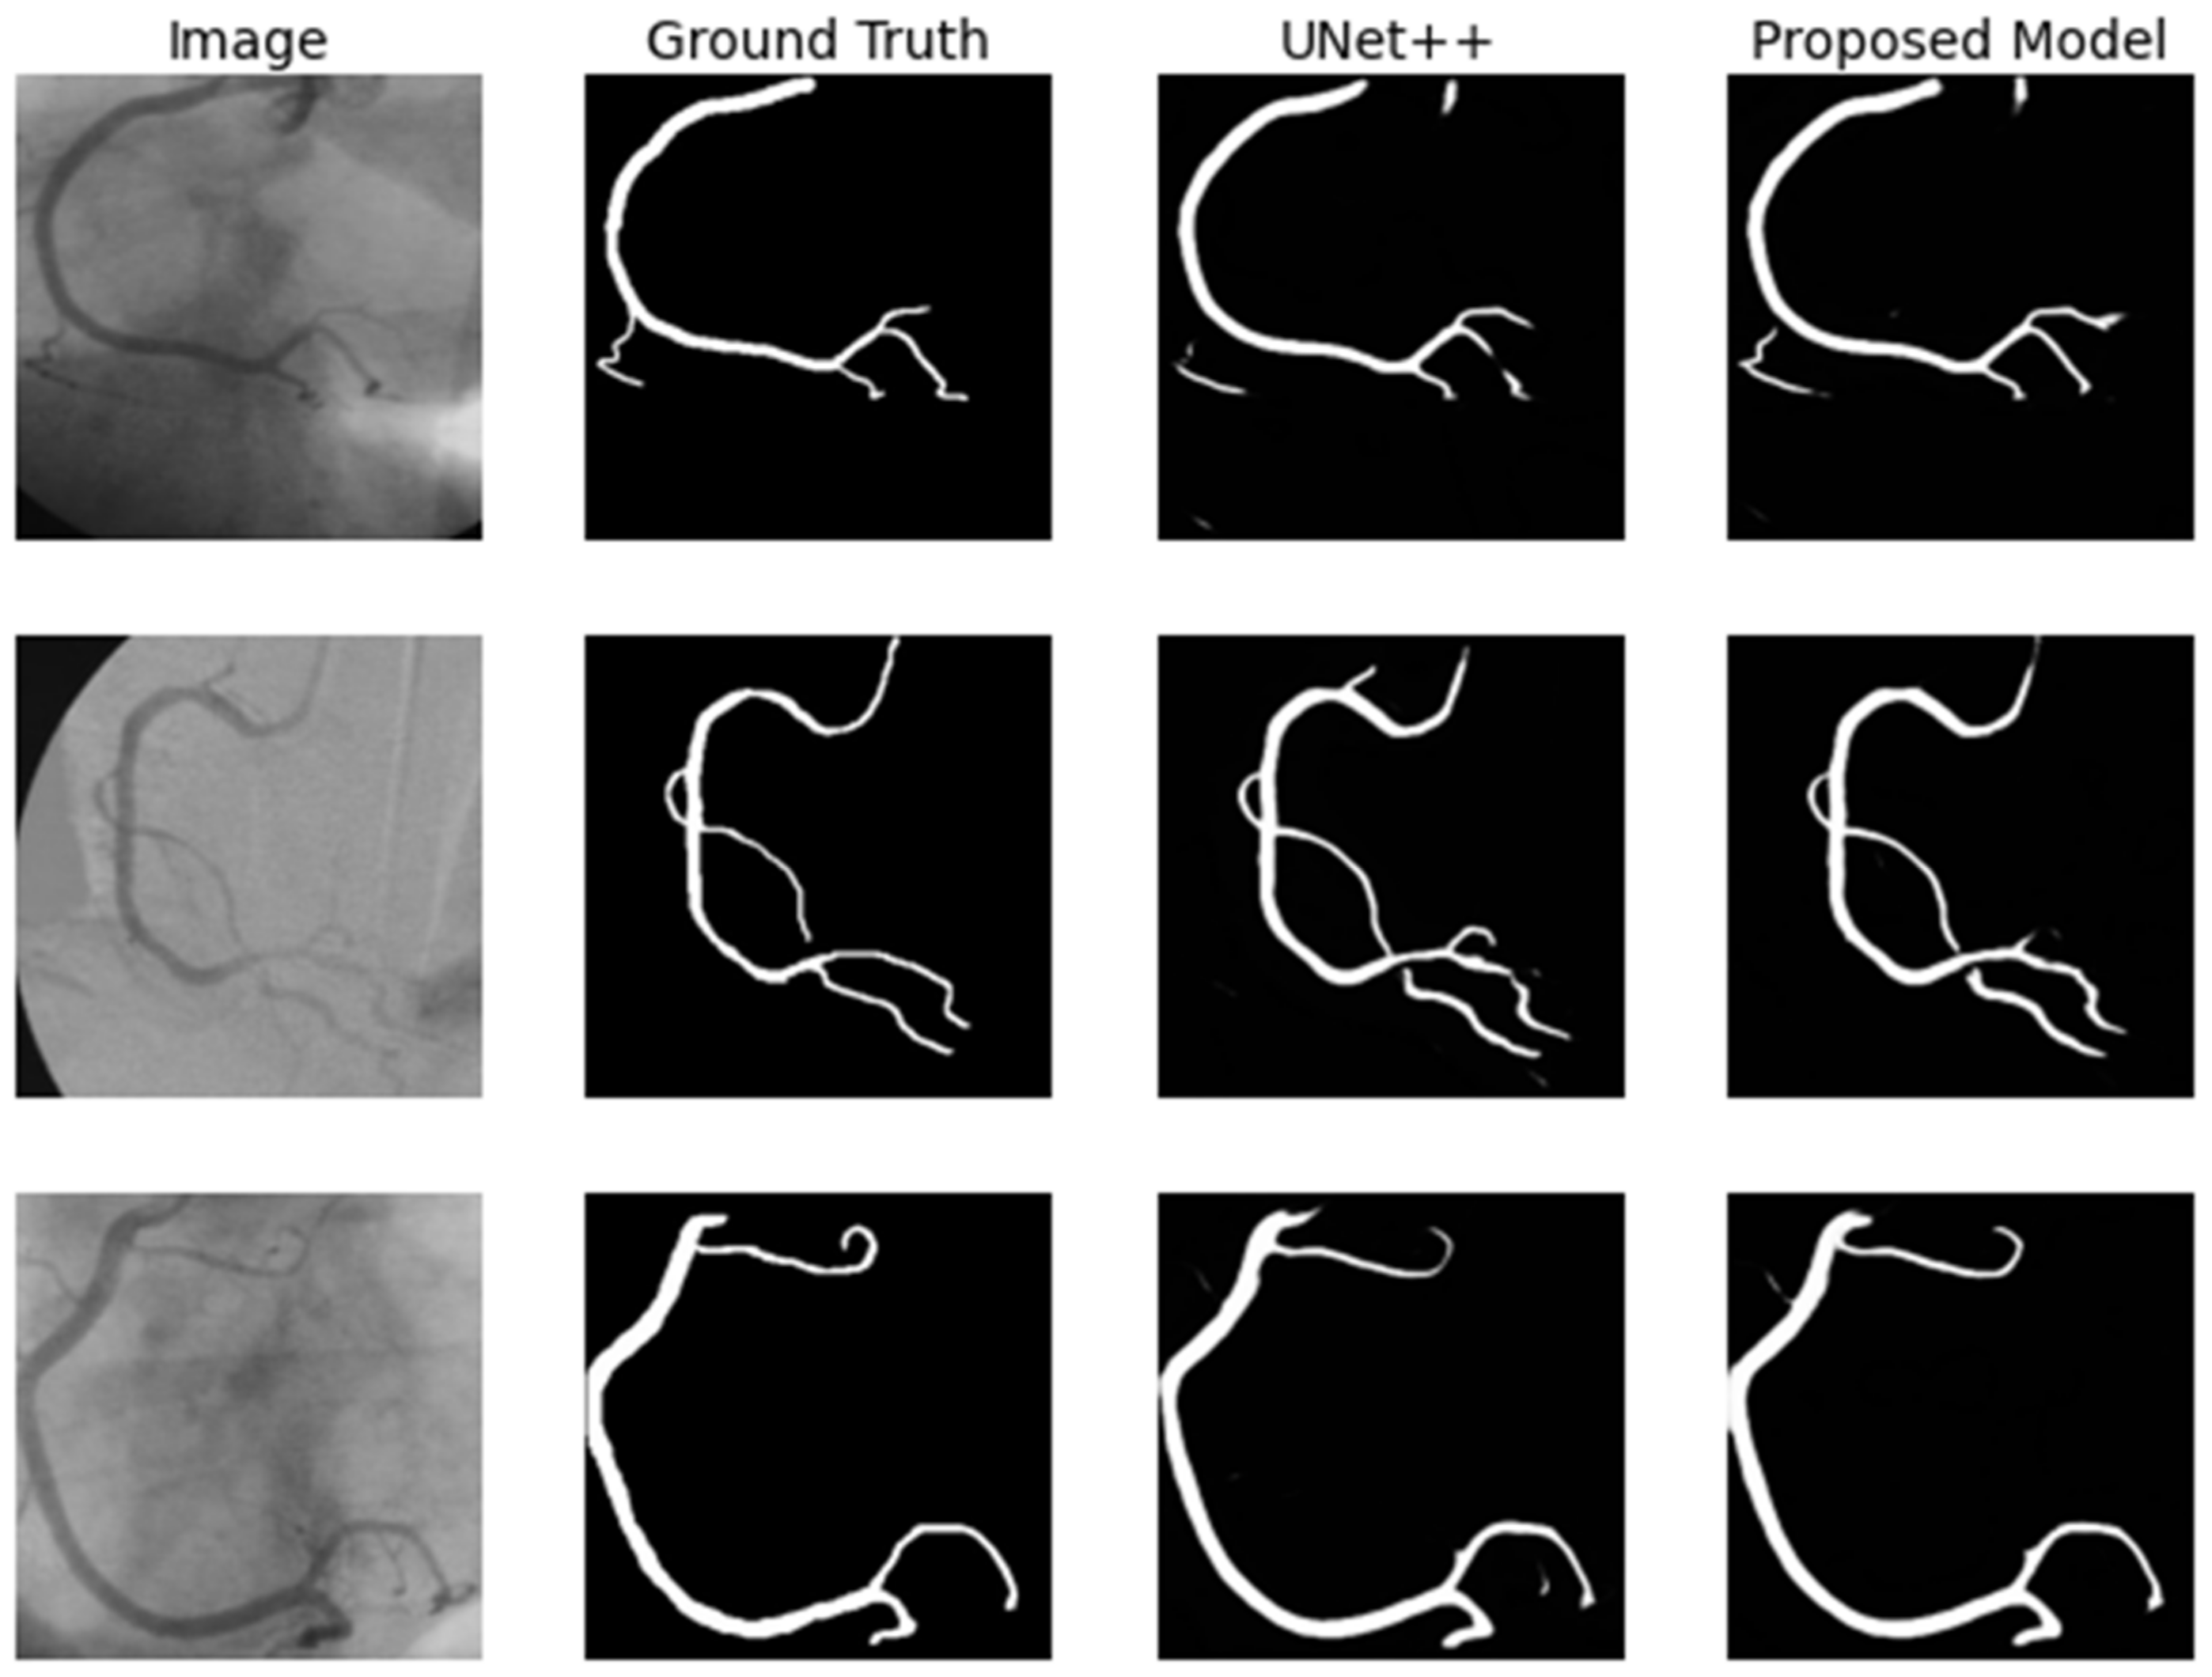

4.3.3. Coronary Artery in Angiography Segmentation

| Methods | F1-Score | SE | IoU (%) | DC (%) |

|---|---|---|---|---|

| FCN | 0.5330 | 0.7250 | 55.12 | 68.34 |

| SegNet | 0.5631 | 0.7506 | 59.81 | 69.40 |

| U-Net | 0.5841 | 0.7865 | 64.15 | 69.17 |

| Attention UNet | 0.5904 | 0.8034 | 65.48 | 69.84 |

| UNet++ | 0.5907 | 0.8119 | 65.11 | 70.02 |

| Attention UNet++ | 0.5901 | 0.8135 | 65.51 | 70.47 |

| Residual Attention UNet++ | 0.6110 | 0.8335 | 66.57 | 72.48 |